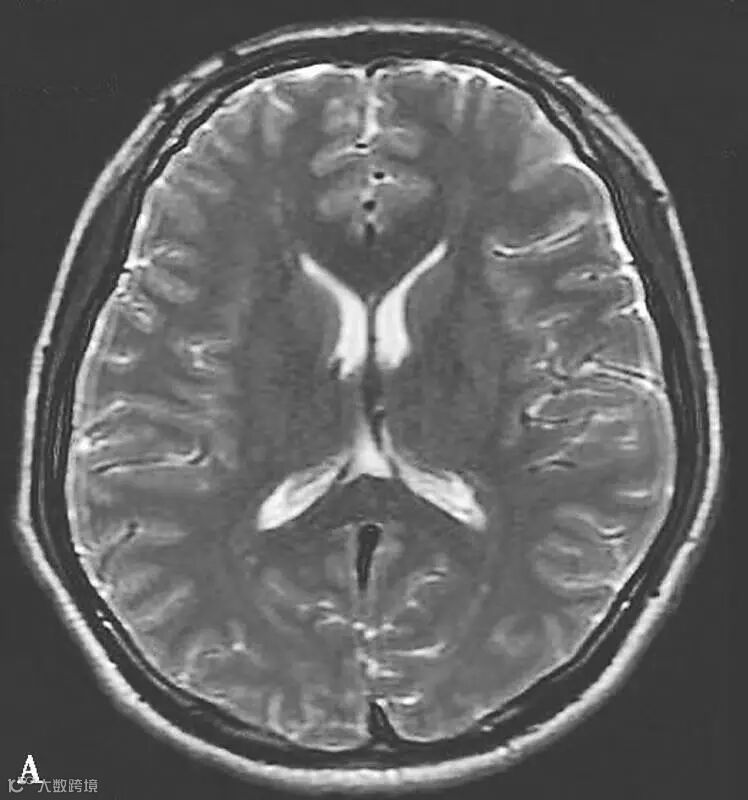

图6-11-2 弥漫性轴索损伤

男,36岁,外伤后2天。A~J(A、B.T2WI,C、D.T1WI,E、F.T2WI-FLAIR,G、H.DWI,I、J.ADC图):双侧额叶、半卵圆中心及胼胝体压部可见多发斑点状等T1稍长T2信号,边缘不清,FLAIR及DWI呈高信号,ADC图病灶信号减低 。